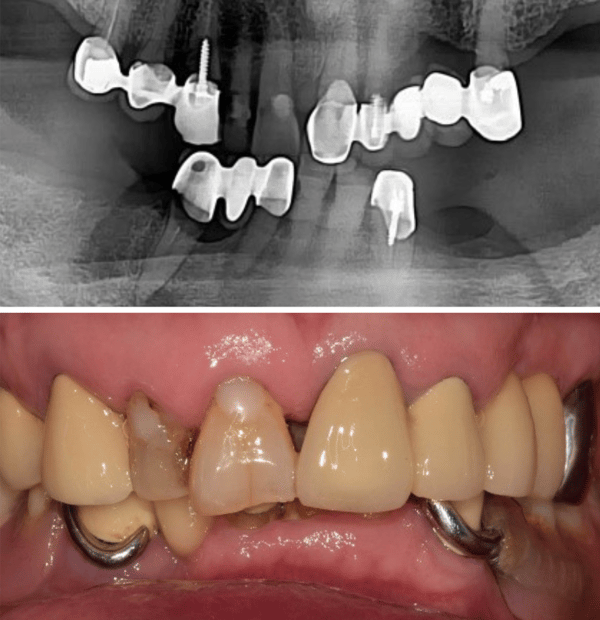

面對殘破不堪的口腔環境

一位長期受牙齒問題困擾的病患走進了診間,他的下顎依賴著一副活動局部假牙維持僅存的咀嚼功能,而右下側的牙橋邊緣已出現繼發性齲齒,多顆牙齒根尖甚至出現病變。對於任何一位經驗豐富的醫師來說,這都是一個棘手的開局。病患渴望植牙,但他提出了一個令許多醫師頭痛的要求:受限於經濟與社交需求,他不願意拔除所有患牙,更不願意在漫長的治療期間經歷無牙的尷尬期。

在數位化介入之前,你可能需要花費大量時間與技工所溝通,反覆進行藻膠印模來確認咬合垂直高度。Jaemin Lee 醫師最初制定了一個穩健的兩階段計畫:先處理左下顎的植牙,保留右側牙橋與 RPD 作為過渡。這是一個合理的打法,透過數位掃描記錄下初始的咬合狀態與軟組織型態,為這場長跑做好了準備。這時,數位檔案就像是一個精準的時空膠囊,完整保存了病患未經破壞前的口腔資訊,這在後續的突發狀況中發揮了決定性的作用。